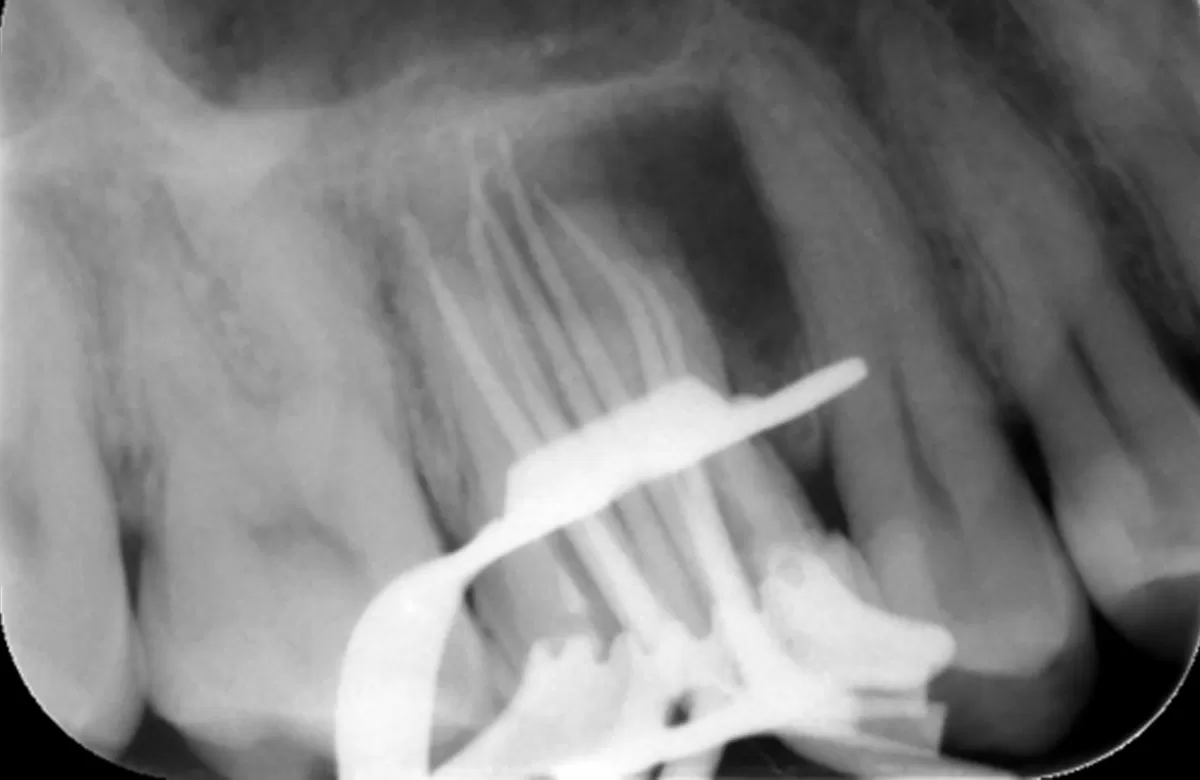

Pre operative periapical radiograph of the tooth 16

| Tooth | 16 |

| Dental history | Patient has had previous root canal treatment over 5 years ago |

| Clinical evaluation | Tooth that is tender to percussion & palpation. Small fluctuant swelling associated with buccal alveolar mucosa |

| Diagnosis | Previously endodontically treated tooth with persisting chronic apical periodontitis |